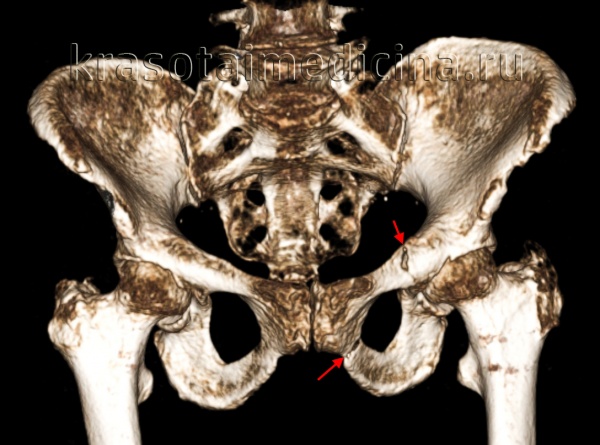

· компьютерная томография – является чувствительной и позволяет оценить целостность заднего отдела таза, а также можно определить размер и локализацию гематомы.

Компьютерная томография. При затруднении четкой интерпретации обзорной рентгенограммы из-за суперпозиции костей назначается компьютерная томография таза.